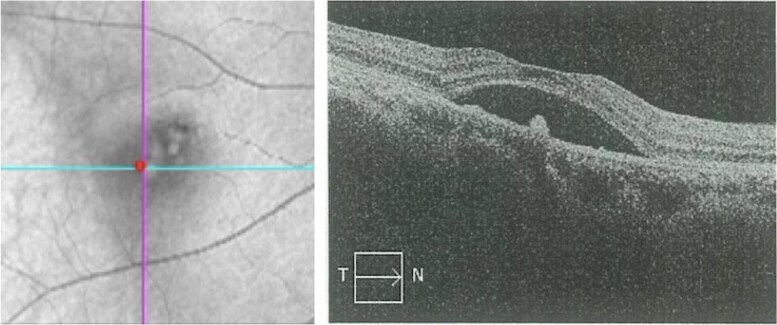

Figure 1.

Optical coherence tomography of the right eye at presentation demonstrating macular edema and serous detachment of the neurosensory retina associated with retinal pigment epithelium detachment, with a subretinal fluid height of 436 μm, consistent with the diagnosis of central serous chorioretinopathy.

A 39-year-old female patient presented with a 7-month history of visual impairment in the right eye (RE) and 2 months’ progressive blurred vision and metamorphopsia. She exhibited progressive weight gain, round face, and hypokalemia. Computed tomography (CT) of the adrenal glands revealed an adenoma. Visual acuity at the time of presentation was 0.5 in the left eye (LE) and 0.6 in the RE, with a diagnosis of serous retinal detachment in the RE. Optical coherence tomography (OCT) of the RE demonstrated serous detachment of the neurosensory retina associated with RPE detachment (Fig. 1), consistent with CSC. The initial clinical signs suggested hypercortisolism, prompting referral to the endocrinology department for further examination.